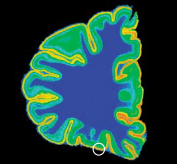

У людей, покончивших жизнь самоубийством, отмечаются анатомические и биохимические изменения в двух отделах головного мозга: в орбитальной префронтальной коре, расположенной над глазами, и в дорсальном ядре шва, находящемся в стволе мозга. Эти изменения указывают на снижение способности головного мозга к выработке и утилизации серотонина нейротрансмиттера, недостаток которого характерен для мозга импульсивных или страдающих тяжелыми депрессиями людей Серотонин вырабатывается нейронами дорсального ядра шва. По их длинным проекциям (синяя стрелка) он достигает орбитальной префронтальной коры. У жертв самоубийства дорсальное ядро шва снабжает орбитальную кору недостаточным количеством серотонина.

Изменения в дорсальном ядре шва

У самоубийц нейроны дорсапьного ядра шва содержат большее количество фермента, ответственного за выработку серотонина (затененная область), чем соответствующий участок мозга человека, умершего по иной причине. Можно предположить, что головной мозг самоубийц содержит максимальное количество серотонина.